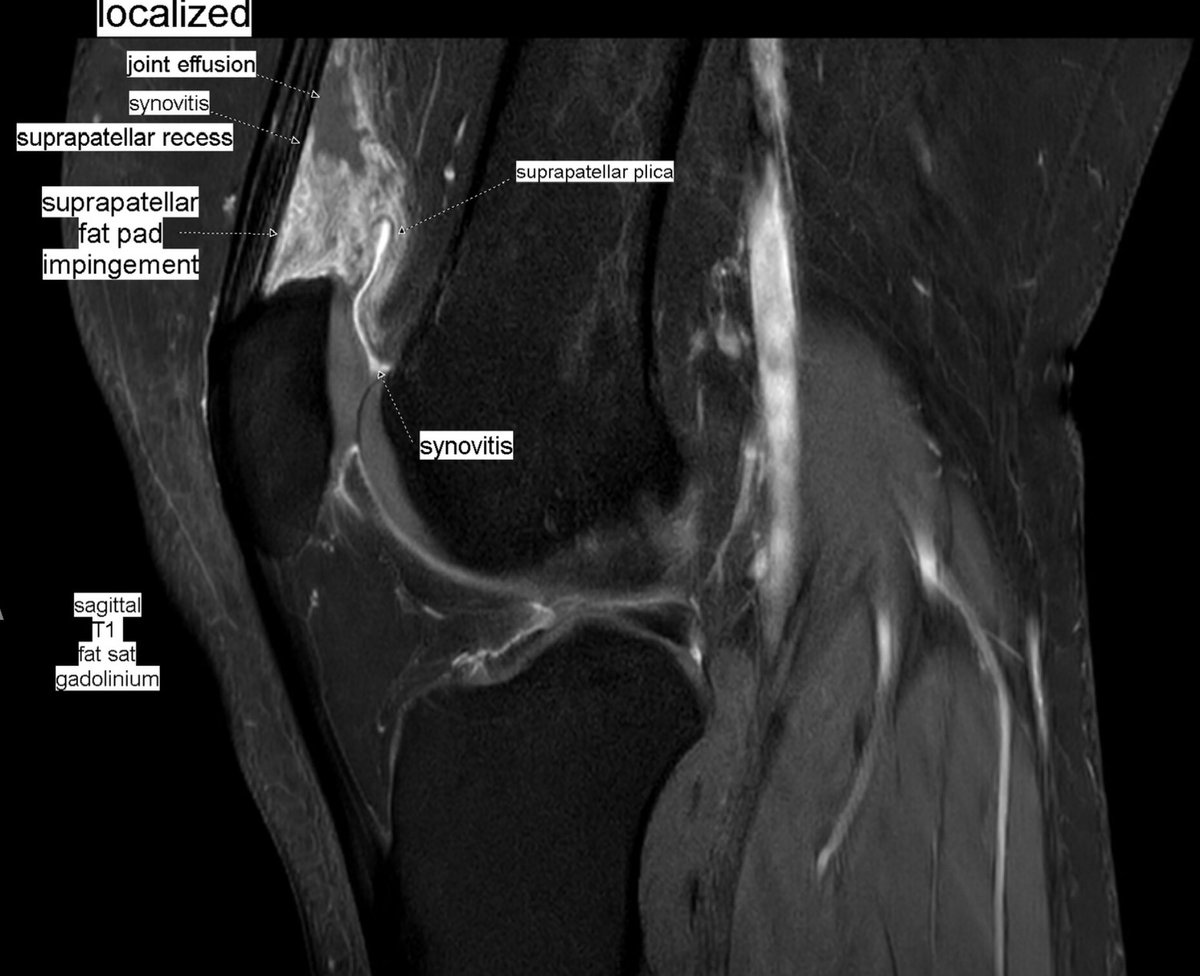

Patient with anterior knee pain. Localized synovitis of suprapatellar recess and suprapatellar fat pad impingement syndrome secondary to a suprapatellar plica: suprapatellar plica syndrome.

#MSKrad#knee#orthopaedics#radiology https://www.ncbi.nlm.nih.gov/pmc/articles/PMC6477514/pdf/main.pdf …pic.twitter.com/fvk7MUuDNt